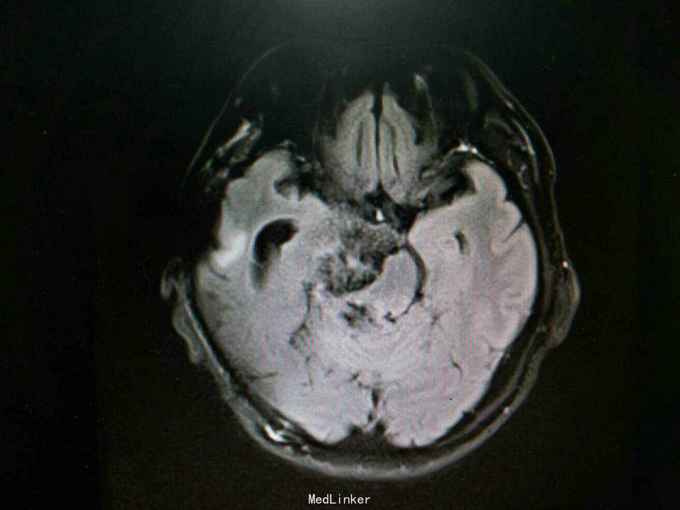

查体:生命体征平稳。神经系统检查:右侧眼睑下垂,左侧眼睑无下垂。肌力 右侧肢体肌力5-级,左侧肢体肌力正常。肌张力: 右上肢肌张力正常,右下肢肌张力正常;左上肢肌张力正常,左下肢肌张力正常。肌营养检查:四肢肌肉无萎缩。共济与平衡检查:正常。外院颅脑CT示右侧桥脑小脑角团片囊性低密度区,性质待定,蝶窦右后方局部骨质缺损代之稍低密度软组织肿块,考虑原肿瘤复发,颅骨呈术后改变,颅脑CT增强示颅内占位性病变(表皮样囊肿?)。入院后行颅脑MRI检查提示: 右侧颞骨岩尖-脚间池-右侧环池-右侧桥小脑角池见片状异常信号影,边界清,形态不规则,呈匍匐状分布,冠状位范围约47mm×29mm。相应右侧颞、脑干明显受压,脑干向左移位。第三脑室略向左移位。右侧额骨、颞骨骨皮质欠连续,呈术后改变。 考虑右侧颞骨岩尖-脚间池-右侧环池-右侧桥小脑角池表皮样囊肿。 右侧颅骨呈术后改变。